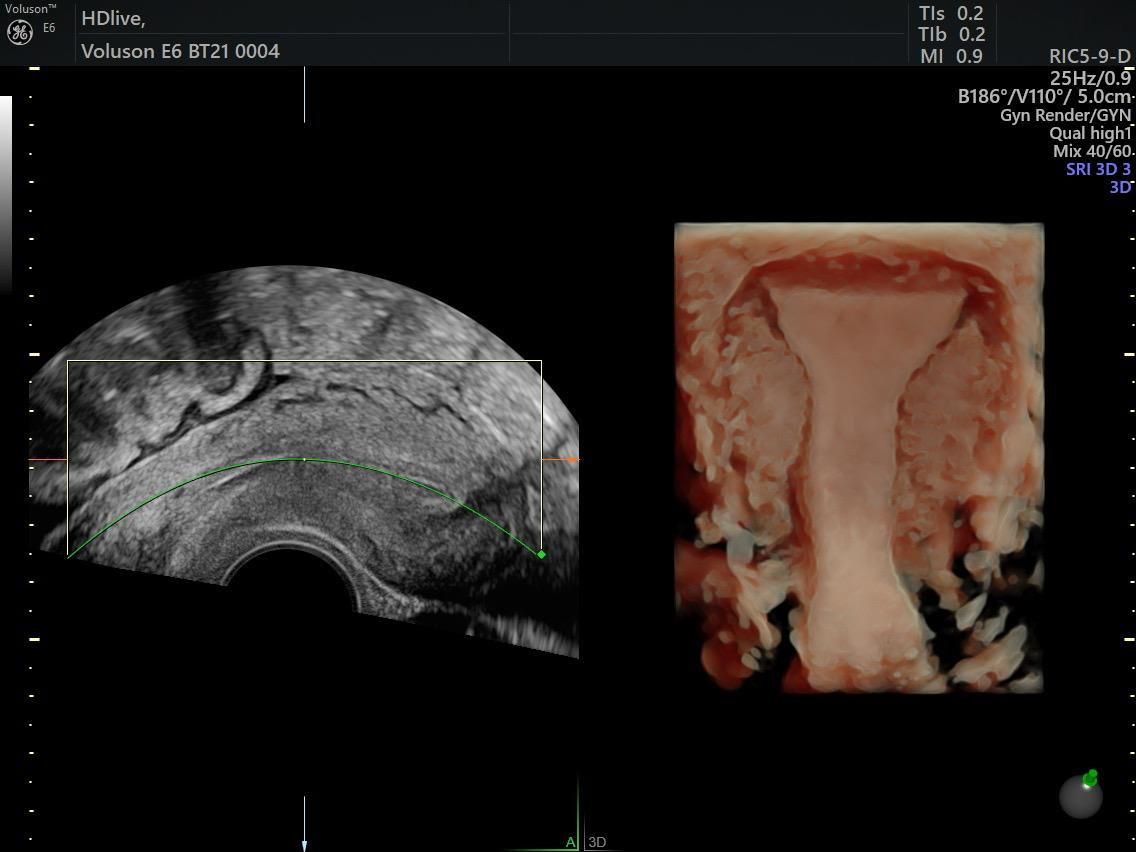

Fetal Medicine

Ultra Sound

Gallery

Images

Photos